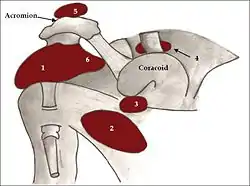

Bursae

A number of small fluid-filled sacs known as synovial bursae are located around the capsule to aid mobility:

- Between the joint capsule and the deltoid muscle is the subacromial-subdeltoid bursa.

- Between the capsule and the acromion is the subacromial bursa.

- The subcoracoid bursa is between the capsule and the coracoid process of the scapula.

- The coracobrachial bursa is between the subscapularis muscle and the tendon of the coracobrachialis muscle.

- Between the capsule and the tendon of the subscapularis muscle is the subscapular bursa, this is also known as the subtendinous bursa of the scapularis.

The supra-acromial bursa does not normally communicate with the shoulder joint.

The shoulder joint is a muscle-dependent joint as it lacks strong ligaments. The primary stabilizers of the shoulder include the biceps brachii on the anterior side of the arm, and tendons of the rotator cuff; which are fused to all sides of the capsule except the inferior margin.[5]

The tendons of the rotator cuff and their respective muscles (supraspinatus muscle, infraspinatus, teres minor, and subscapularis) stabilize and fix the joint.[4] The supraspinatus, infraspinatus and teres minor muscles aid in abduction and external rotation.